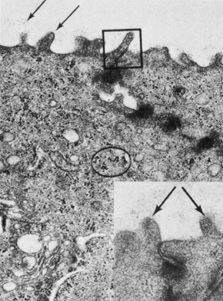

Fig. 6. Transmission electron micrograph showing the apical membrane of the surface epithelium and intercellular junctions along the lateral membranes. Arrows indicate fine, branching filaments of the glycocalyx emerging from the surface microvilli. A tight junction (box) and densely staining desmosomes are seen along the lateral membranes. Glycogen is evident (circle), as well as numerous vesicles (23,000×). Inset: Arrows point to microvilli from two adjacent surface cells (64,500×). (Courtesy of Drs. Rodrigues, Waring, Hackett, and Donohoo.)

The margins of the apical cell membrane possess the important tight junctions surrounding the cell circumference near the apical margin.20 This junction complex is the correlate of the paracellular pathway of high resistance to ion flow. The lateral and basal membranes of the apical cells have gap junctions, numerous desmosomal junctions, and numerous membrane-bound vesicles. The cytoplasm contains a flattened nucleus (which probably disintegrates prior to desquamation), few organelles, and a notable increase in tonofilaments compared with the underlying cells. There are some aggregates of glycogen granules, small mitochondria, sparsely distributed free ribosomes, and poorly developed Golgi's complexes. Cytoplasmic vesicles are fairly numerous.21